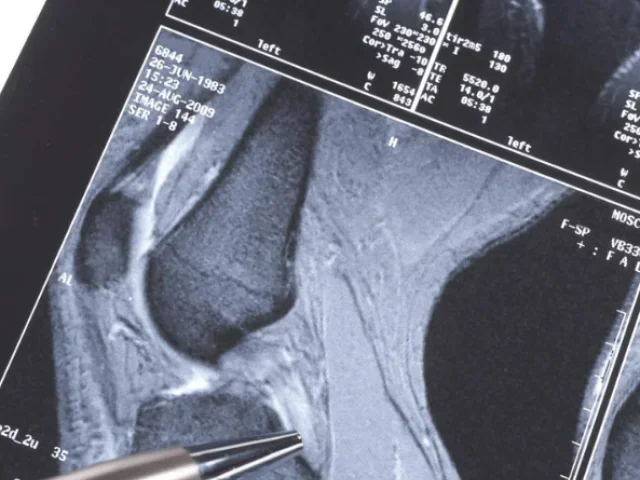

La resonancia magnética lumbar es una técnica de diagnóstico por que permite obtener imágenes detalladas de la región lumbar y sacra de la columna vertebral. Es utilizada para evaluar con precisión hernias de disco, lesiones en nervios y tejidos circundantes, así como para el diagnóstico condiciones como la espondilosis y estenosis espinal, la planificación de procedimientos quirúrgicos y el monitoreod e padecimientos crónicos de la columna lumbar.